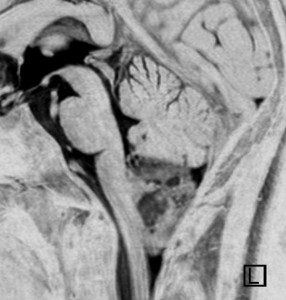

幼児の巨大な上衣腫です。左ルシュカ孔から延髄を取り囲む様に小脳延髄角槽に進展しています。最も典型的で治療が難しいタイプです。これはT2強調画像ですが,ガドリニウム増強されないものでした。

左が術前,右が術後です。脳底動脈の周囲が摘出できませんでした。幼児ですが手術後には局所照射をするしか方法がありません。

病理組織診断では退形成性上衣腫,MIB-1は40%以上にも達します。

この様なEPN-PFAは,脳外科の先生と小児科の先生が最も苦労するものですが,予後は極めて不良です。